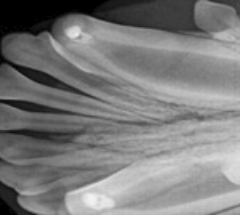

Tannstillingsfeil

I løpet av det første 9 måneder er det veldig mye som skjer i munnen hos valper og kattunger. Hos valper må 28 melketenner falle ut og 42 permanent tenner bryte frem. Hos kattunger skal 26 melketenner falle ut og 28 permanente tenner komme inn.

I tillegg skal underkjeven og hodeskallen vokse i størrelse og tykkelse. I det fleste tilfeller vil denne dynamiske prosessen gi et normalt bitt for hunden og katten. Av og til kan en valp eller kattunge utvikle en tannstillingsfeil.

Hvis bittfeilen resulterer i en skade eller betennelse i munnhulen må det korrigeres. Type behandling er basert på dyrets alder og grad av feilen: alt fra partiell pulpektomi (les videre på denne siden), trekking av tenner som hindrer riktig utvikling av bittet eller å operere ut melketenner som har ikke falt ut på riktig tidspunkt. Det kan være behov for flere besøk for å bekrefte at kjeven og permanente tenner utvikler seg til et funksjonelt og smertefritt bitt for den voksen hund eller katt.

Tannrøntgenbilder tas. Veiledning og informasjon til eieren.